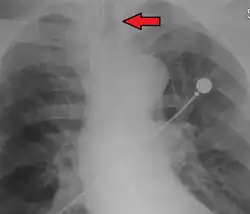

Ideally, at least one of the methods utilized for confirming tracheal tube placement will be a measuring instrument. Waveform capnography has emerged as the gold standard for the confirmation of tube placement within the trachea. Other methods relying on instruments include the use of a colorimetric end-tidal carbon dioxide detector, a self-inflating esophageal bulb, or an esophageal detection device.[35] The distal tip of a properly positioned tracheal tube will be located in the mid-trachea, roughly 2 cm (1 in) above the bifurcation of the carina; this can be confirmed by chest x-ray. If it is inserted too far into the trachea (beyond the carina), the tip of the tracheal tube is likely to be within the right main bronchus—a situation often referred to as a "right mainstem intubation". In this situation, the left lung may be unable to participate in ventilation, which can lead to decreased oxygen content due to ventilation/perfusion mismatch.[36]